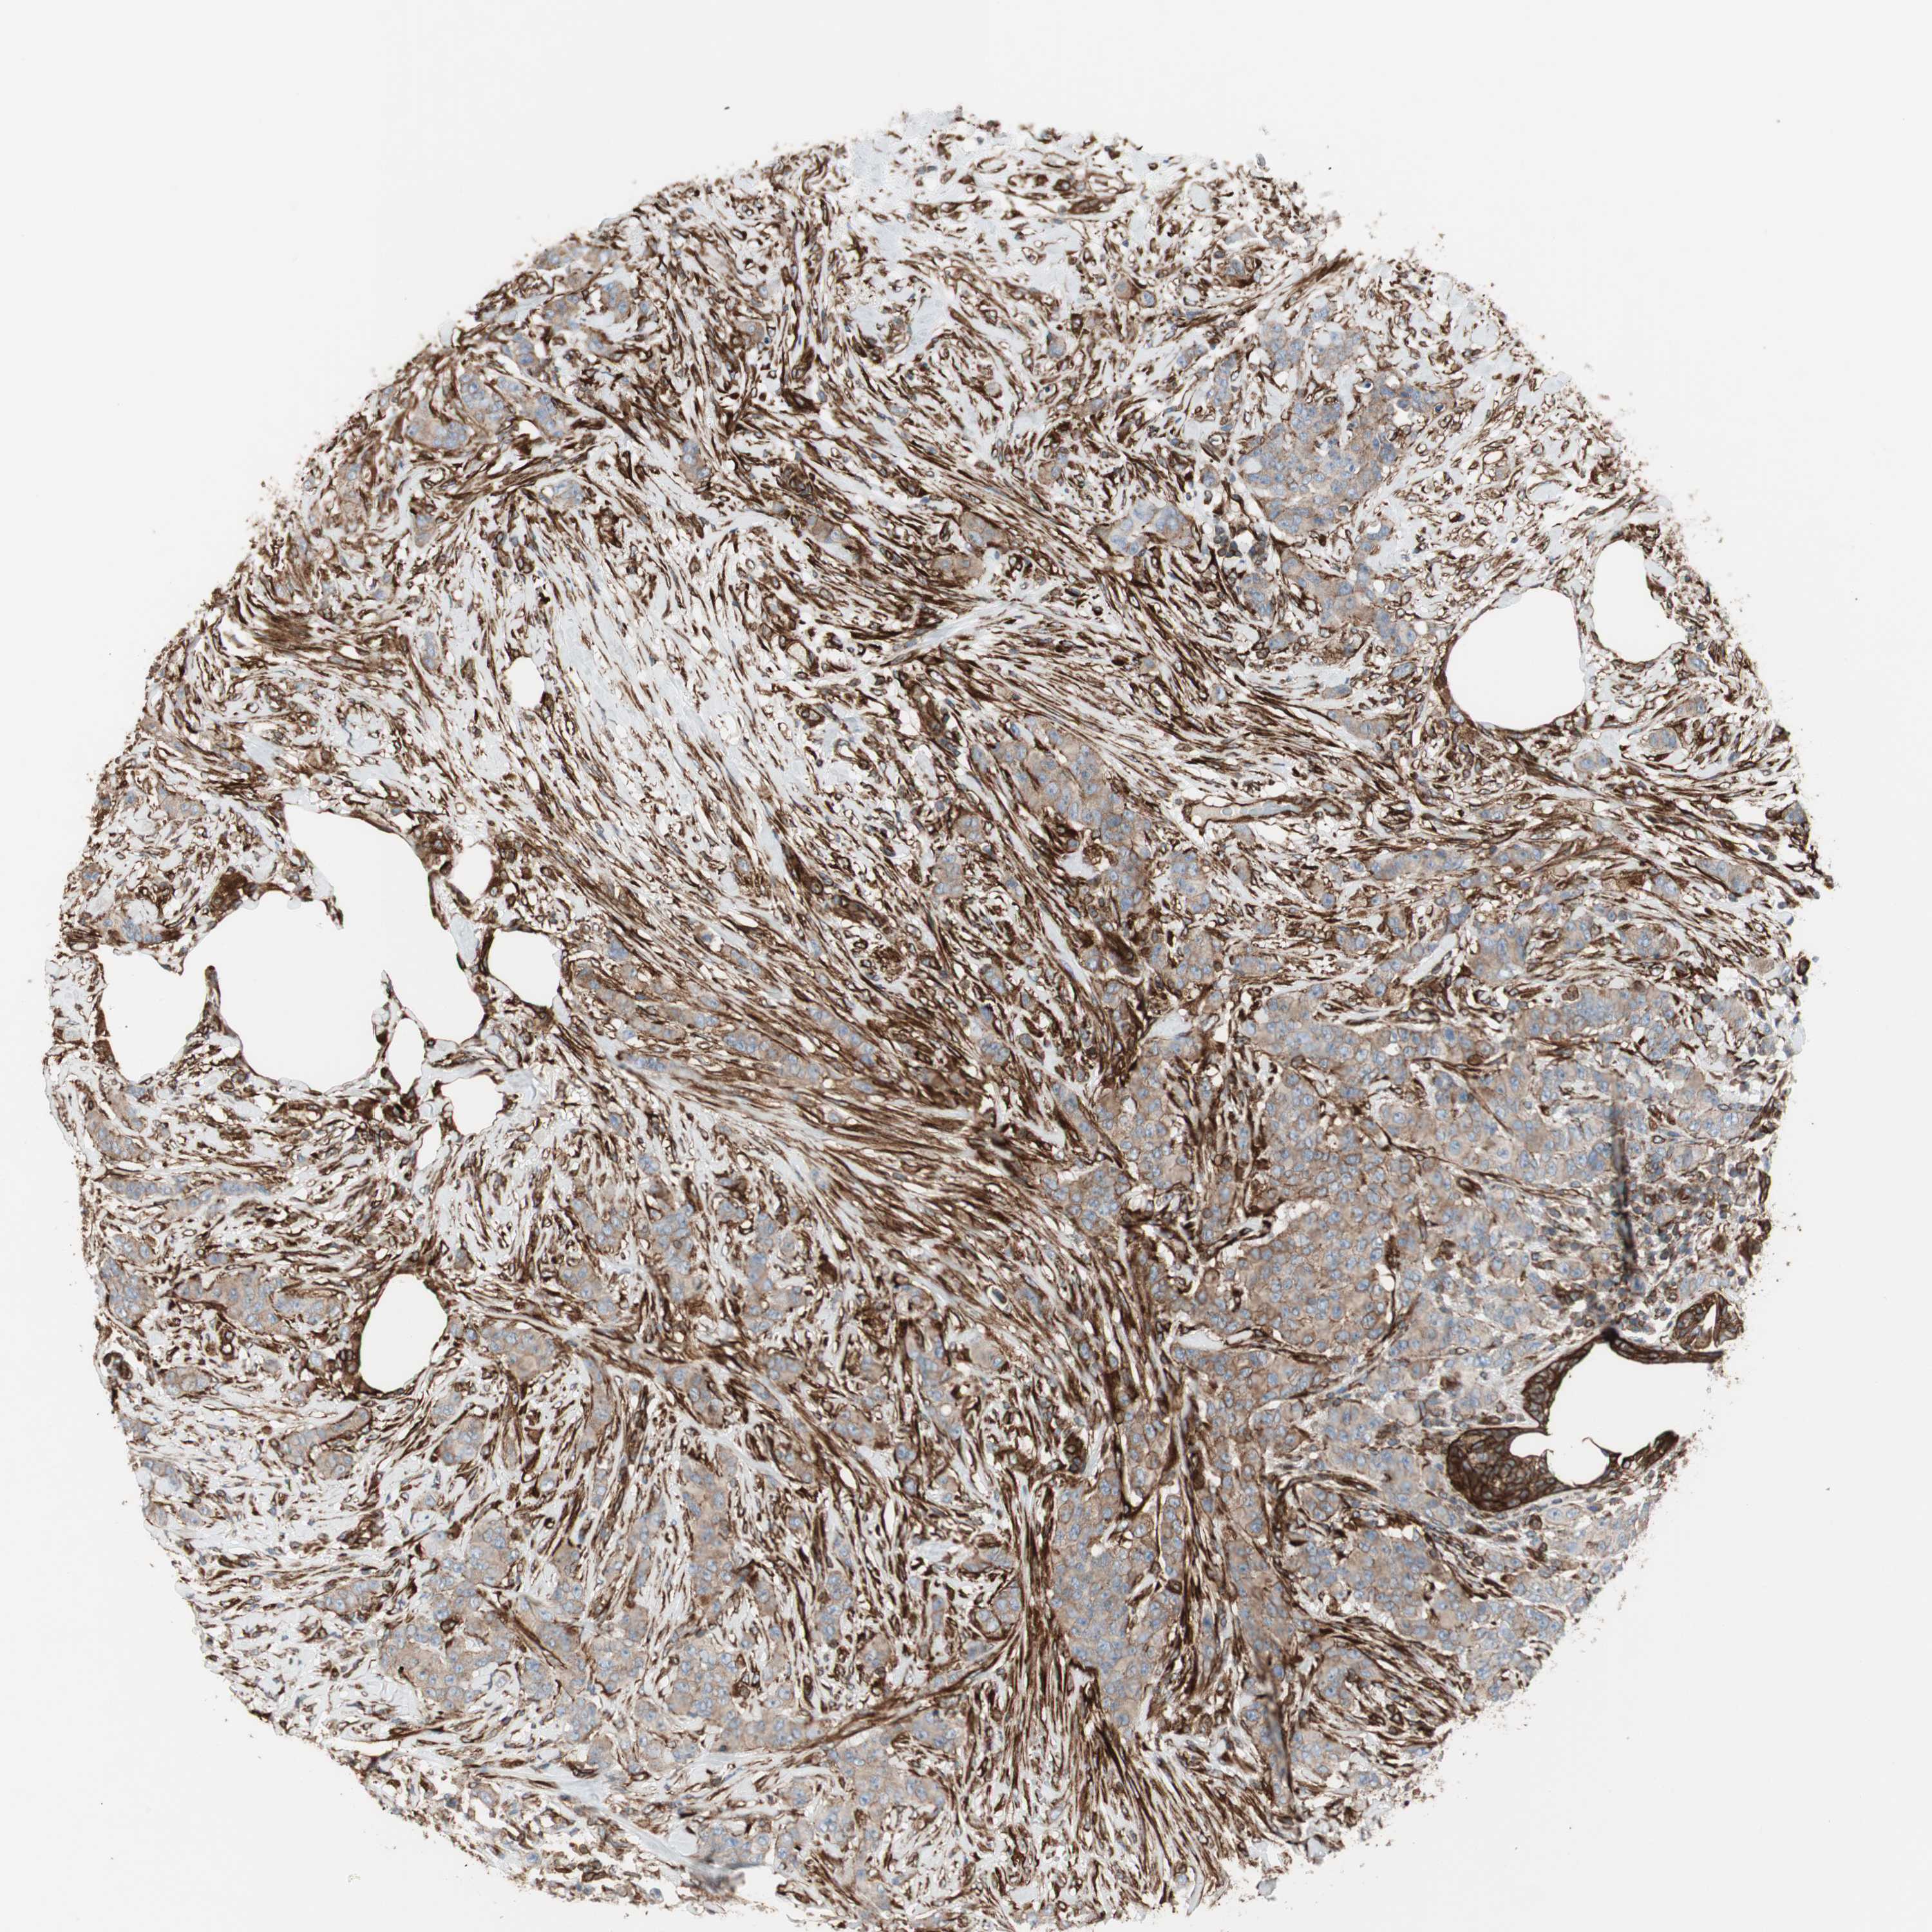

CANCER BREAST CANCER Show tissue menu

BRCA TCGA BRCA VALIDATION PROTEIN EXPRESSION